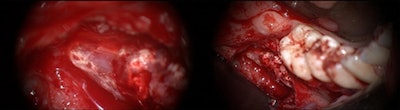

A cone-beam computed tomography (CBCT) scan confirmed widespread extrusion of the root canal sealer in this region. Upon surgical exploration and decompression of the woman's right inferior alveolar nerve, clinicians found an avascular and fibrotic nerve with virtually no normal neuronal structure. They also saw evidence of foreign material, which was found to be root canal sealer, in contact with the epineurium and within the nerve trunk.